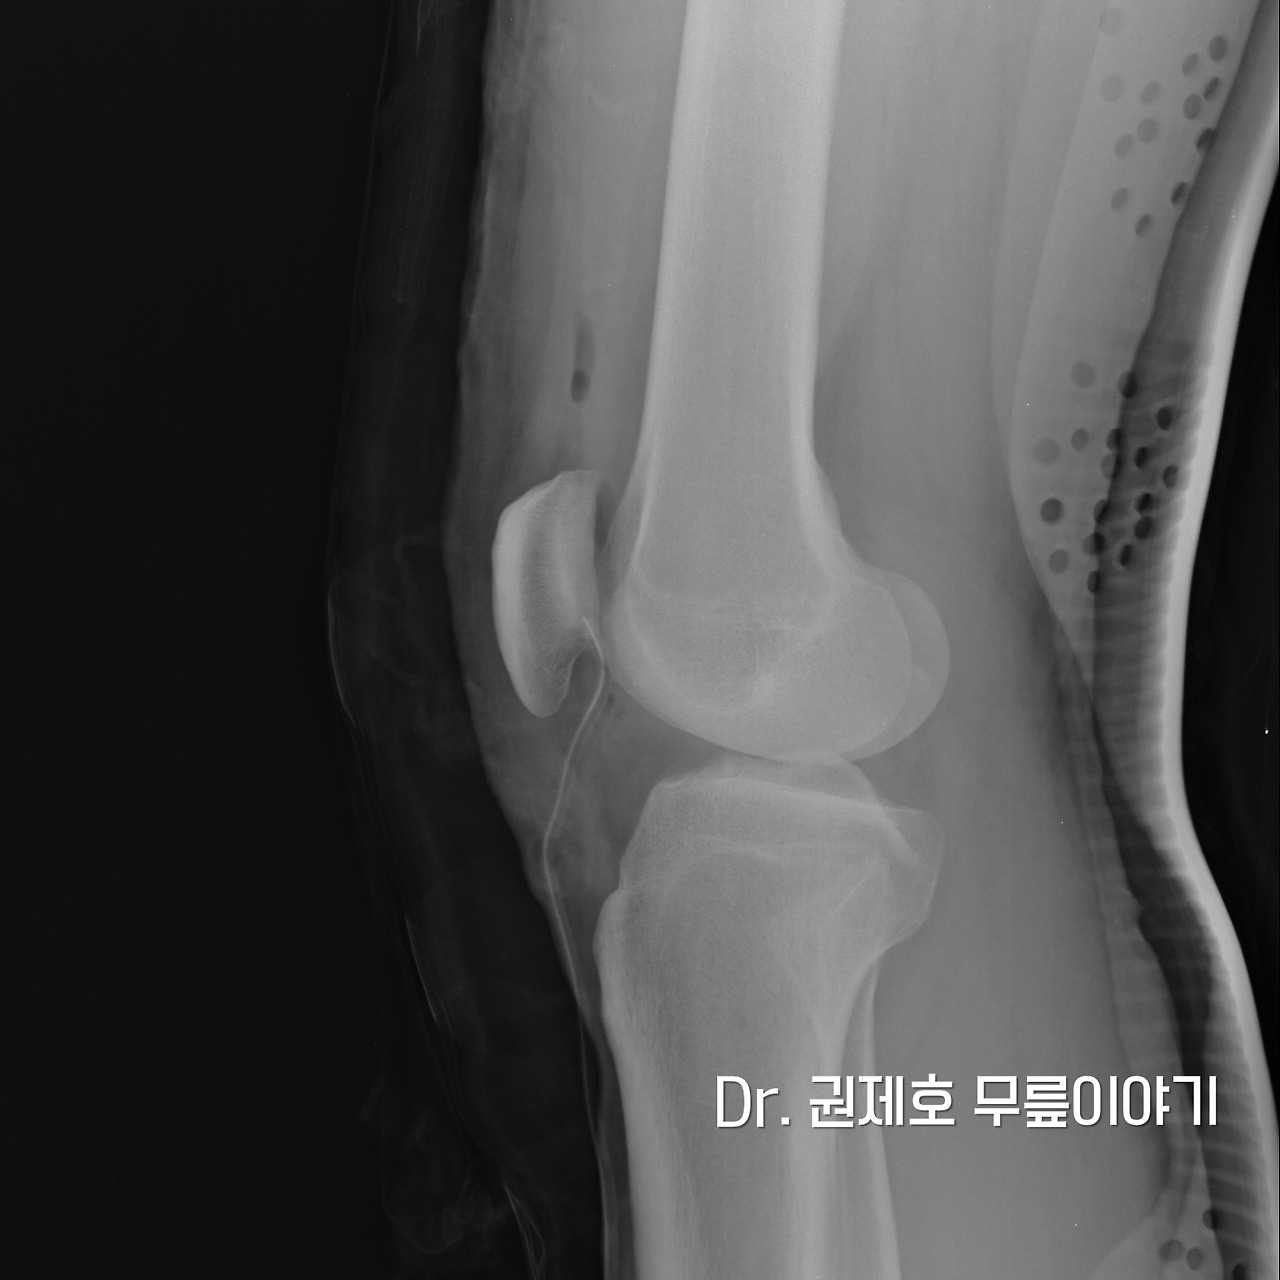

무릎 관절경을 모두 마치고 사진을 찍으면 무릎 속에 선이 하나 보이게 된다. 바로 배액관이다. 무릎 관절경을 하고 나면 무릎 관절에 피가 고이기 때문에 이를 제거하는 방법이다.